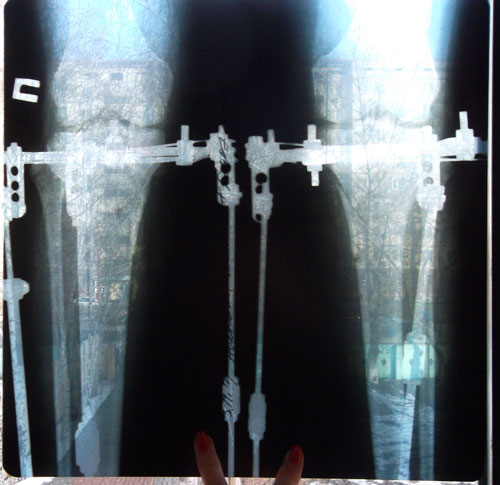

Дата операции 16.10.2014г.

Дата снятия аппаратов 30.01.2015г.

Срок лечения 102 дня.